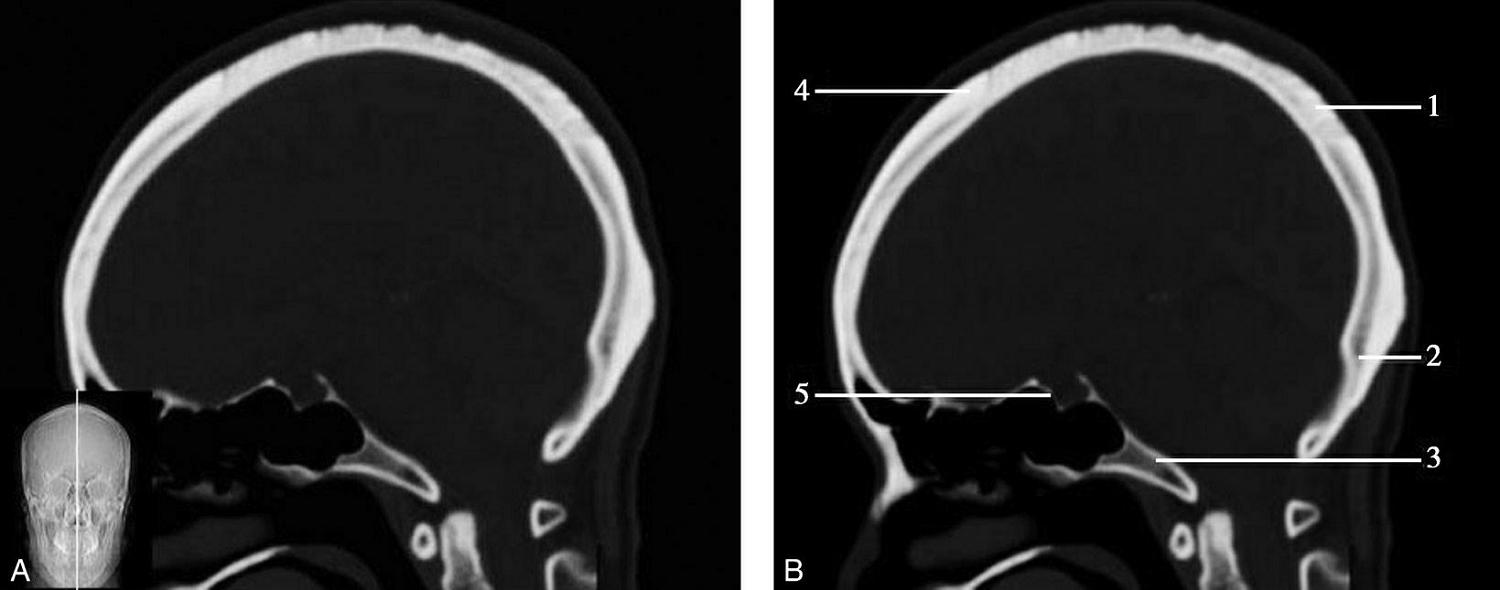

重要结构:胼胝体、垂体、中脑导水管、扣带回、中央沟、第三脑室、斜坡(图1-2-59、图1-2-60)。

图1-2-59 正中矢状面CT

A.矢状面;B.矢状面标注

1.中央沟;2.扣带回;3.胼胝体体部;4.侧脑室;5.中脑;6.胼胝体膝部;7.穹隆;8.第三脑室;9.胼胝体压部;10.垂体;11.中脑导水管;12.第四脑室;13.脑桥;14.蝶窦;15.斜坡;16.小脑扁桃体;17.延髓

图1-2-60 正中矢状面骨窗CT

1.顶骨;2.枕骨;3.斜坡;4.额骨;5.蝶鞍

此层面可显示胼胝体全貌,它位于层面中央区域,是呈上凸下凹的弧形结构,由前向后分为嘴、膝、体和压四部分。扣带回环绕胼胝体上方,扣带沟位于扣带回的上方。大脑半球中部和后部分别可见较深且恒定的中央沟和顶枕沟。中央沟为是额叶顶叶分界标志。

胼胝体下方为侧脑室及穹窿,第三脑室借穹窿与前上方的侧脑室体部分开,背侧丘脑的内侧面以及中脑顶盖分别为第三脑室的外侧壁和底。第三脑室向前籍室间孔与侧脑室相通,向下经中脑导水管通第四脑室。中脑腔狭窄呈管状,即称为中脑导水管,中脑导水管畸形,常见者为导水管的分叉畸形和狭窄,其次可见中脑导水管膈膜,造成先天性脑积水。

脑干由中脑、脑桥和延髓组成,自第三脑室底向下后稍斜行,移行于颈髓。由上至下,脑干腹侧可见脚间池、桥前池和延髓池,脑干背侧可见大脑大静脉池、四叠体池和小脑延髓池。

垂体位于蝶鞍内,其前部为腺垂体,后上部分为神经垂体。垂体下方为鞍底及蝶窦,上缘因鞍膈存在而平直,垂体借垂体柄向上连于丘脑下部。垂体的前上方见视交叉和视束。斜坡作为前颅窝底的重要组成部分与多个重要结构相比邻,矢状位呈三角形,颅内肿瘤或颅外鼻咽部恶性肿瘤均可侵犯至此,原发肿瘤常见为脊索瘤。小脑幕居枕叶和小脑之间,向后下连接窦汇,向前至中脑后方游离,称小脑幕切迹。小脑幕下方为小脑扁桃体。成年人小脑扁桃体下缘由枕骨大孔向下疝入椎管超过5mm称为Chiari畸形,以矢状位显示最佳。